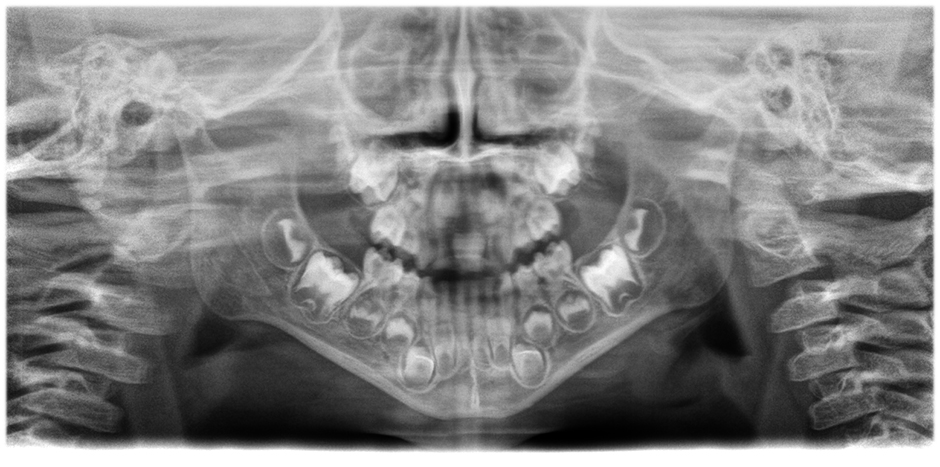

• Images panoramiques d'une clarté et d'une définition exceptionnelles

avec le système innovant d'autofocus à 21 couches intégré de manière transparente à une correction du positionnement du patient.

Déplacez le curseur pour voir la différence (image de gauche sans, image de droite avec autofocus et correction de la position du patient)